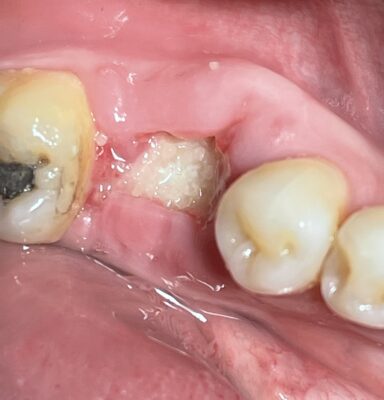

Jedediah posted an update a year ago

OK Dojo Peeps. Some of you wanted to see some suturing techniques for socket preservations that we went over during the last study club meeting so here you go. Lots of different ways that you can do it. A lot of it just comes down to preference. This one is an inverted figure 8 with multiple passes. I find this to be a very useful…